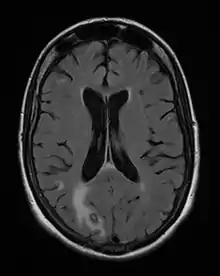

Diagnosis of toxoplasmosis in humans is made by biological, serological, histological, or molecular methods, or by some combination of the above.[57] Toxoplasmosis can be difficult to distinguish from primary central nervous system lymphoma. It mimics several other infectious diseases so clinical signs are non-specific and are not sufficiently characteristic for a definite diagnosis. As a result, the diagnosis is made by a trial of therapy (pyrimethamine, sulfadiazine, and folinic acid (USAN: leucovorin)), if the drugs produce no effect clinically and no improvement on repeat imaging.

- Nawaz Khan, A (2015). "Imaging in CNS Toxoplasmosis". Medscape Web Site.